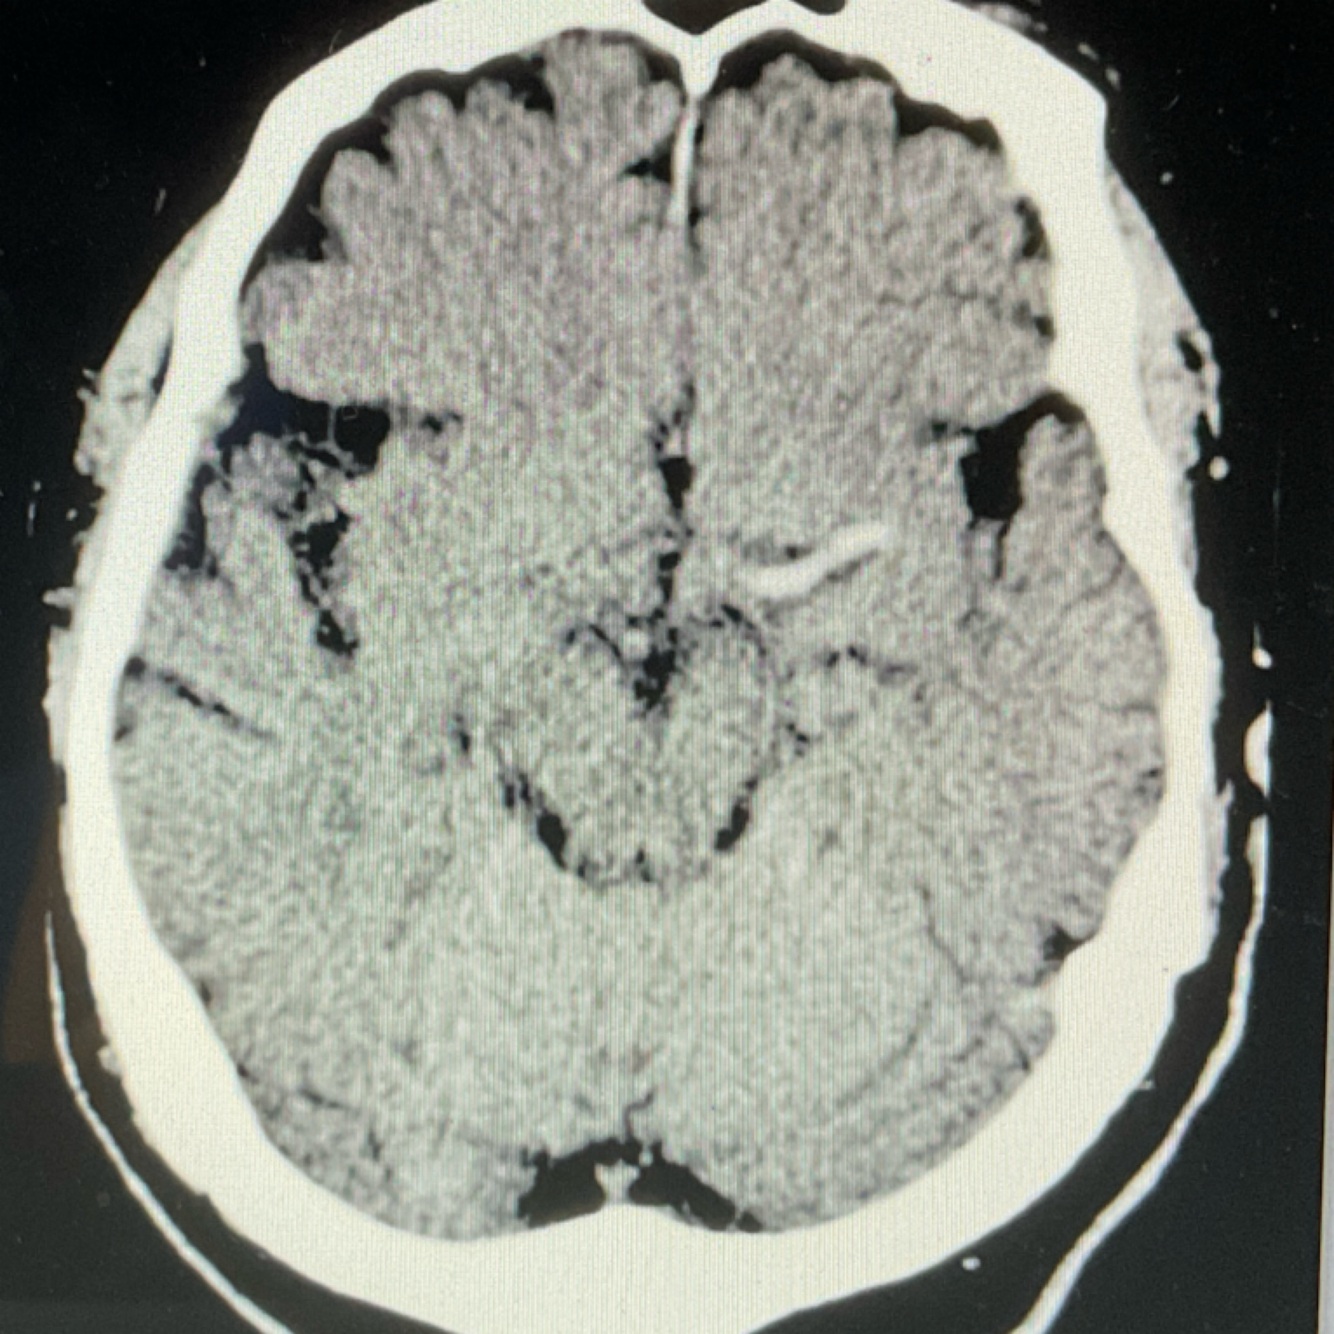

10

Q

A

EVC isquémico subagudo